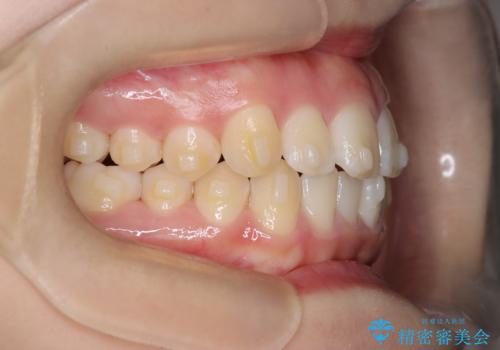

- 患者様は、**下の前歯のがたつき(叢生)**を気にされて来院されました。

できるだけ目立たずに治療を進めたいというご希望があったため、インビザラインによるマウスピース矯正をご提案しました。

診査の結果、インビザラインでの対応が可能と判断し、全体の咬合バランスにも配慮した上で、治療計画を立てました。